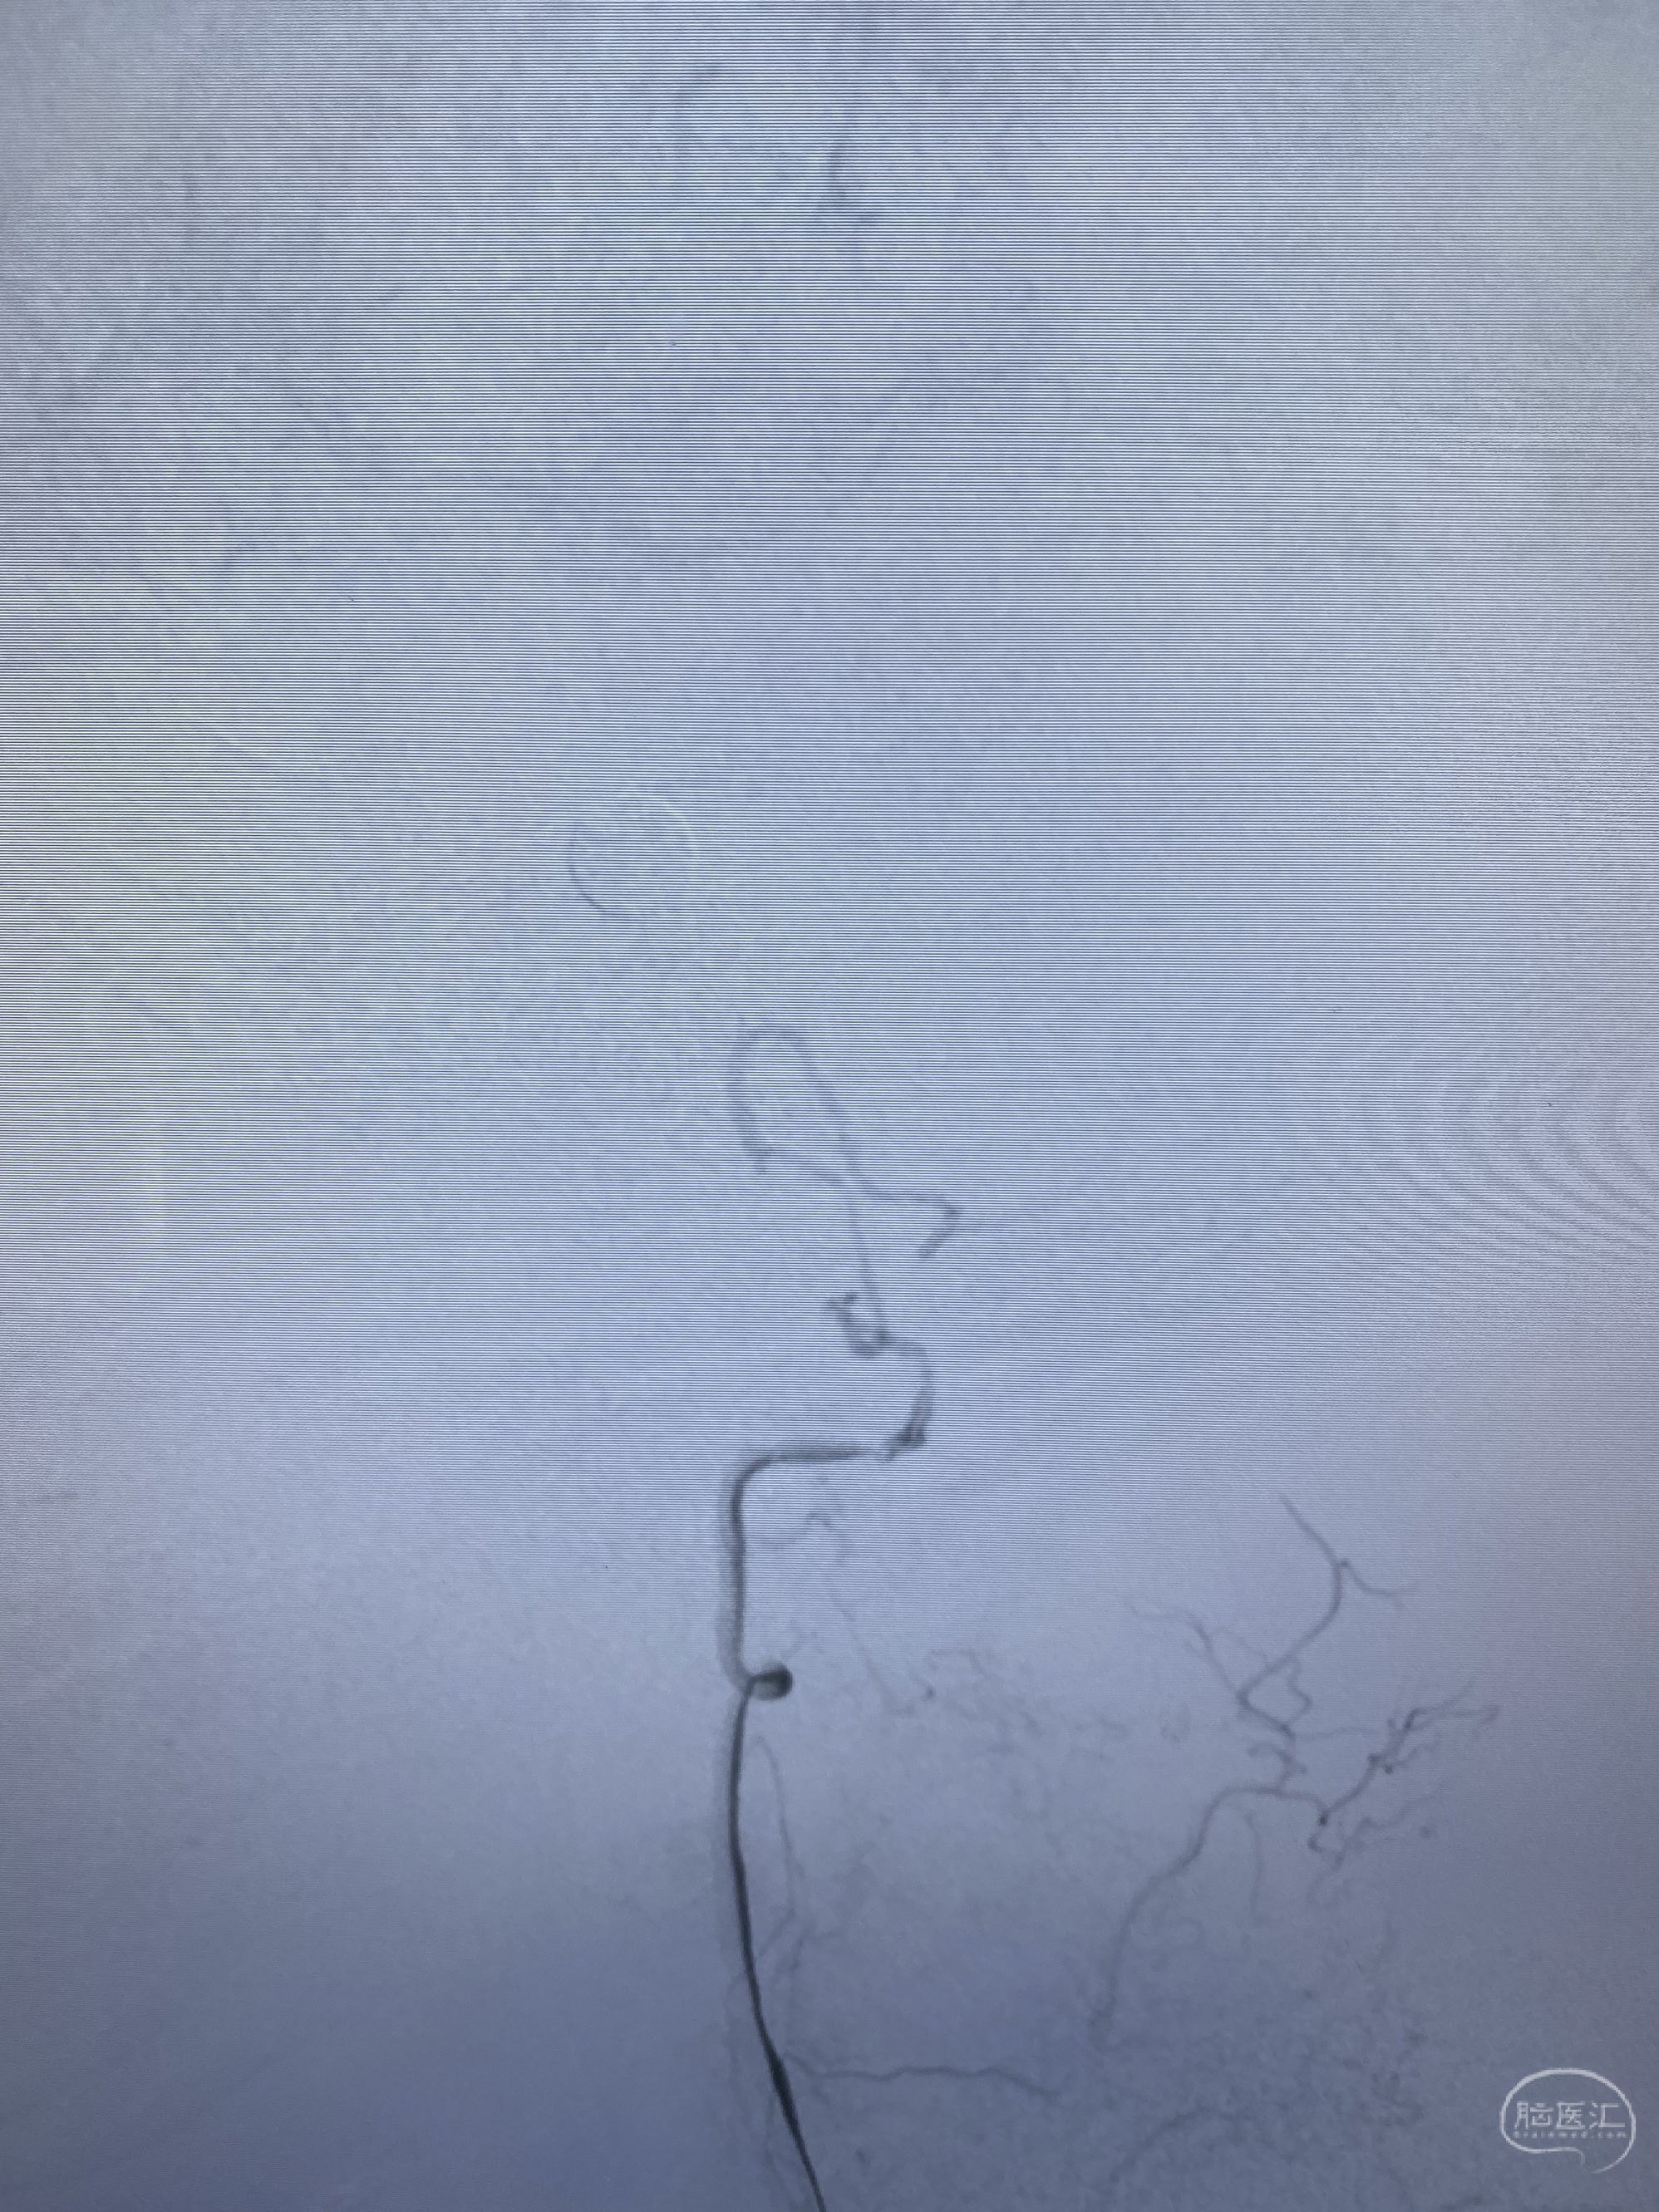

今日手术,TJG,M62Y,一期左侧颈动脉狭窄支架植入,二期椎动脉V4段多发夹层动脉瘤伴狭窄,常规支架辅助栓塞方法复杂又危险,血流导向装置植入快捷又安全。南阳市中心医院神经内科脑血管病介入团队pipeline flexFD植入两人导师资格。

椎动脉颅内段多发夹层动脉瘤伴载瘤动脉狭窄pipeline flex植入

今日手术,TJG,M62Y,一期左侧颈动脉狭窄支架植入,二期椎动脉V4段多发夹层动脉瘤伴狭窄,常规支架辅助栓塞方法复杂又危险,血流导向装置植入快捷又安全。南阳市中心医院神经内科脑血管病介入团队pipeline flexFD植入两人导师资格。